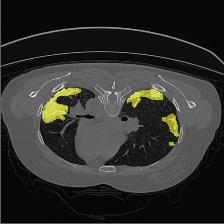

Medical image segmentation is one of the most fundamental tasks concerning medical information analysis. Various solutions have been proposed so far, including many deep learning-based techniques, such as U-Net, FC-DenseNet, etc. However, high-precision medical image segmentation remains a highly challenging task due to the existence of inherent magnification and distortion in medical images as well as the presence of lesions with similar density to normal tissues. In this paper, we propose TFCNs (Transformers for Fully Convolutional denseNets) to tackle the problem by introducing ResLinear-Transformer (RL-Transformer) and Convolutional Linear Attention Block (CLAB) to FC-DenseNet. TFCNs is not only able to utilize more latent information from the CT images for feature extraction, but also can capture and disseminate semantic features and filter non-semantic features more effectively through the CLAB module. Our experimental results show that TFCNs can achieve state-of-the-art performance with dice scores of 83.72\% on the Synapse dataset. In addition, we evaluate the robustness of TFCNs for lesion area effects on the COVID-19 public datasets. The Python code will be made publicly available on https://github.com/HUANGLIZI/TFCNs.

翻译:医学图像分解是医学信息分析的最根本任务之一,到目前为止已经提出了各种解决办法,包括许多深层次的学习技术,如U-Net、FC-DenseNet等。 然而,高精度医学图像分解由于医疗图像中存在固有的放大和扭曲,以及存在与正常组织密度相似的损伤,因此仍是一项极具挑战性的任务。在本文件中,我们建议TFCN(全面革命稠密网络的传输者)通过向FC-DenseNet引进ResLear-Transerferent(R-Transerfor)和Culvacial线性关注区(CLAB)来解决这一问题。TFCN不仅能够利用CT图像中更多的潜在信息来提取特征,而且还能够通过CLAB模块更有效地捕捉和传播语性特征和过滤非神经性特征。我们的实验结果表明,TFCN可以在Syapseion/SymblyDDS上以83CN-72 ⁇ 的分数实现状态。此外,我们在Synapse-DRIS数据设置上,我们还将评估CUTFTFI/LIS的可靠度。